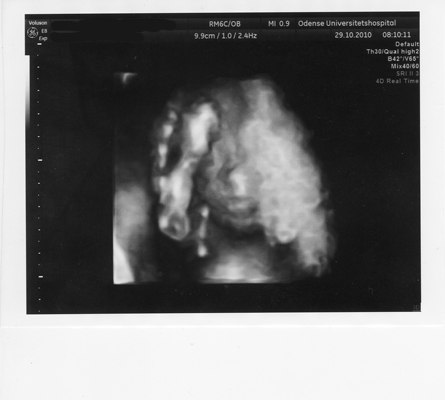

Men det var ellers en noget livlig unge jeg har tumlende rundt derinde, den vendte og drejede sig i et væk, og hun mente at påtrods af at min moderkage ligger foran så kan det ikke vare længe før jeg kan mærke den lille vildbasse. Hun var meget tilfreds og sagde at den trives godt, vokser som den skal og alt så ud til at være hvor det skulle være og der var alle fingre og tæer.

Men desværre kunne hun ikke se kønnet sagde hun, for hver gang hun var lige ved og næsten kunne se det så vendte den lille røver sig om så vi kun kunne se en røv eller ryggen. Nå sagde jeg så, jamen så skulle vi nok bare ikke vide det, så er det bare en hemmelighed. Så skulle hun til at pakke væk, men.... så tog hun lige scanneren på igen - ej jeg kigger lige en gang mere sagde hun... uh sagde jeg tror måske at hvis jeg umiddelbart skal give et bud så skal i have en lille pige.

Nå det blev langt, men i skal da også lige have et par billeder af vidunderet uanset om det er en lille pige eller en lille dreng.